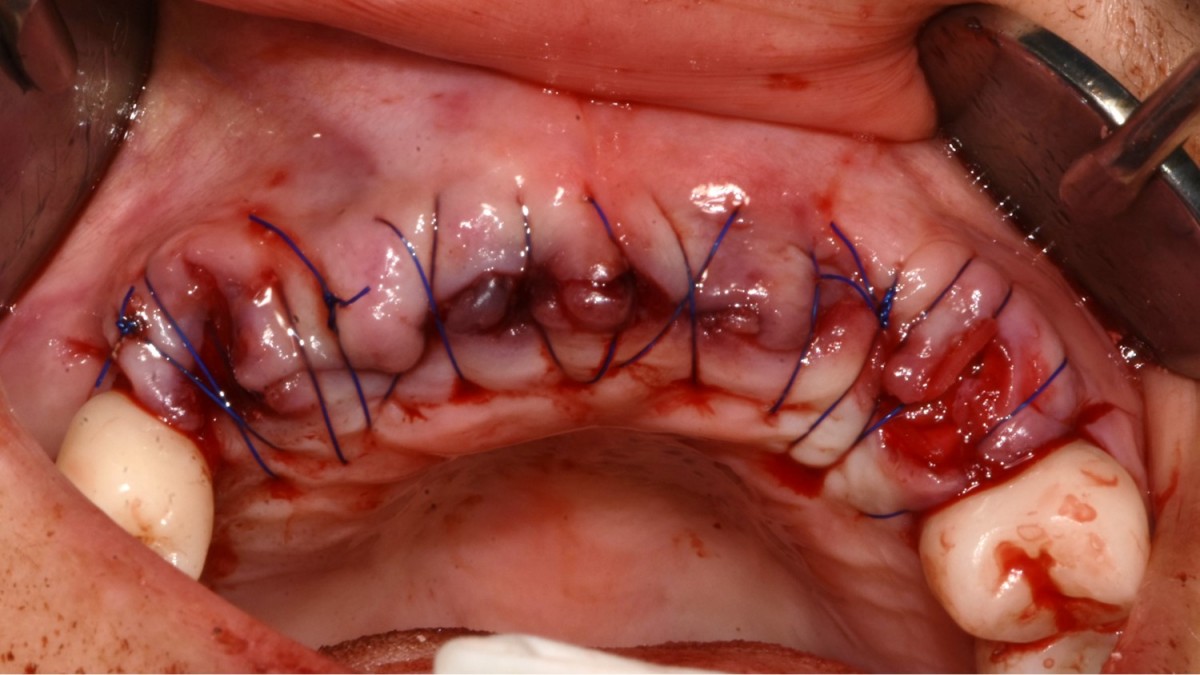

▲Implant placement GBR

▲GBR(Xenograft).